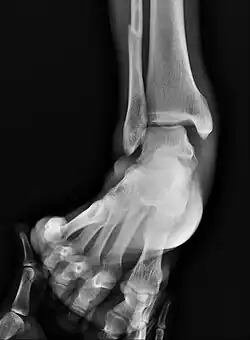

On X-rays, there can be a fracture of the medial malleolus, the lateral malleolus, and/or of the anterior/posterior margin of the distal tibia. The posterior margin (known as the posterior malleolus) is much more frequently injured than the anterior aspect of the distal tibia. If both the lateral and medial malleoli are broken, this is called a bimalleolar fracture (some of them are called Pott's fractures). If the posterior malleolus is also fractured, this is called a trimalleolar fracture.